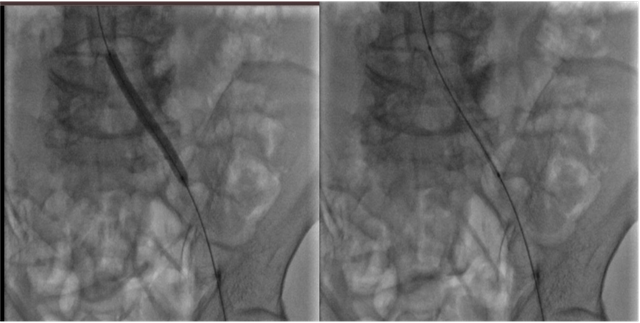

Nong bóng và đặt Stent động mạch chậu bên trái cho bệnh nhân

Chụp lại động mạch chậu trái sau nong bóng và đặt stent

Nhờ ứng dụng kỹ các kỹ thuật can thiệp nâng cao và sự thành thạo trong kinh nghiệm của ekip, ca phẫu thuật đã diễn ra thành công. Bệnh nhân được nong bóng và đặt 1 Stent 06x58mm vào động mạch chậu trái và nong bóng động mạch đùi nông bên trái.